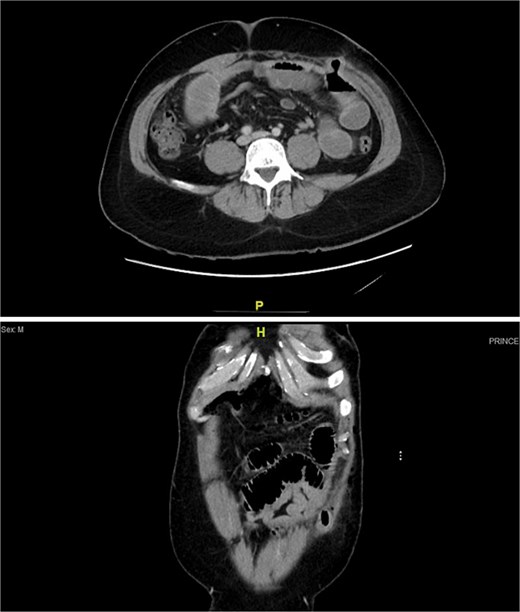

On Day 1, he reported persistent abdominal pain without passage of stool or flatus. By Day 3, symptoms worsened. CT abdomen showed dilated small bowel loops (up to 4 cm) with air–fluid levels, but no definite transition point or ischemia (Fig. 1).

Contrast-enhanced CT scan showing dilated small bowel loops with multiple air–fluid levels, consistent with small bowel obstruction. No clear transition point is identified.